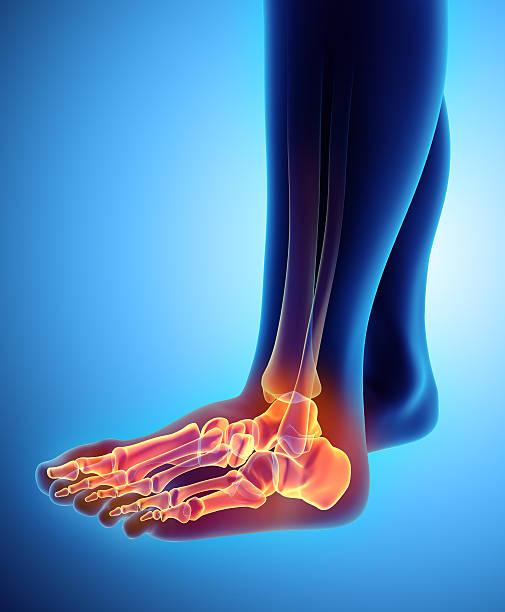

발뒤꿈치가 아픈 이유 3. 점액낭염

발뒤꿈치가 아픈 이유 세 번째는 점액낭염입니다. 점액낭은 아킬레스건의 움직임을 부드럽게 해주는데 이 역시 반복된 충격을 가하기 때문에 발뒤꿈치에 통증이 생길 수 있습니다. 다만 아킬레스건과 다르게 평소에도 통증이 지속되기 때문에 지속적인 관리를 해야합니다.

발뒤꿈치가 아픈 이유 4. 지방 패드 위축 증후군

발뒤꿈치가 아픈 이유 네 번째는 지방 패드 위축 증후군입니다. 발뒤꿈치와 발 앞부분에는 피부와 뼈 사이에 탄력 있는 지방 조직이 있어 페달링의 충격을 흡수합니다. 여기에 너무 많은 압력을 가하거나 나이가 들어감에 따라 지방조직이 퇴화되어 수축하면 완충액이 제대로 기능하지 못해 염증과 통증을 유발한하는데 지방 패드 위축 증후군은 처음에 발을 디딜 때는 괜찮으나 한참을 걷다보면 통증을 느낄 수 있으며 이로 인해 발바닥의 피부가 두꺼워져 지방 패드의 수축을 보상하기 위해 굳은살이 형성됩니다.